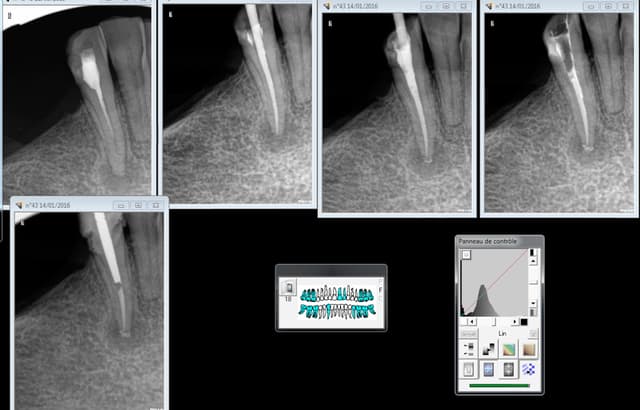

Bon vaut mieux faire les endos ic coiffes dans la séance et disposer de 3 bagues rouges sur l'unit. -)))))

Ici 40 mn de l'endo à la provisoire, mais il n'y a qu'une seule dent, par groupe de 3 on améliore la rentabilité et on peut descendre à 25- 30 mn par dent. Se concentrer sur les mono radiculées, les molaires font baisser la moyenne à cause de l'endo, en plus c'est au fond rien à branler ca ne se voit pas. -)))))

Chicot chef de centre. -))))